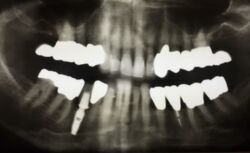

Die Kronen und Brücken, die man auf dem aktuellen Röntgenbild sieht sind aus dem Jahr 1999, damit inzwischen 17 Jahre im Mund. Freiendbrücken, wie hier zu sehen würden wir heute nicht mehr herstellen lassen und eingliedern. Diese Konstruktionen stammten noch aus einer Zeit, in der wir nicht in der Lage waren derartige Situationen mit Implantaten zu versorgen.

Noch interessanter, das Implantat 45, seinerzeit noch ein sogenanntes "Pressimplantat" der Firma Bicon wurde am 13.11.2003 inseriert, ist inzwischen also auch seit 12 Jahren in Funktion.

Das Implantat ist nach wie vor knöchern voll integriert und es gibt keinen Anlass anzunehmen, dass das Implantat in den nächsten 12 Jahren einen Funktionsverlust erwarten ließe.